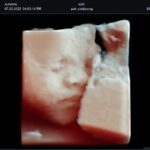

| Software Disponibles OB/GIN: | 3D/4D convexo y endocavitario, Live HQ, Volume Advance, Auto Translucencia Nucal (NT), X+ Auto Biometry, X+ Follicle, Silhouette View |